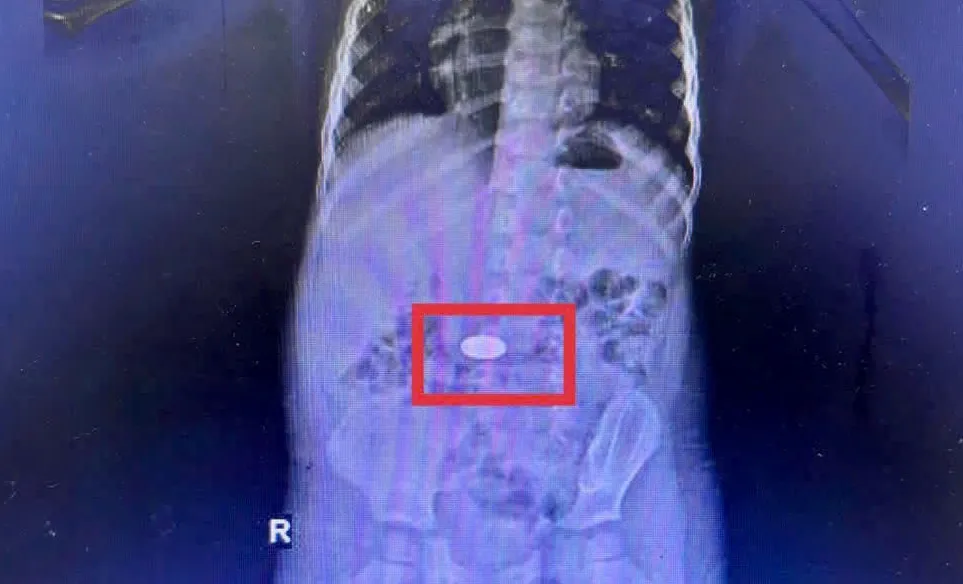

Gia đình cho biết bé vô tình nuốt đồng xu khi đang chơi. Kết quả chụp CT cho thấy dị vật nằm trong dạ dày. Các bác sĩ đã khẩn trương nội soi và lấy ra đồng xu vào rạng sáng 26-11. Bé đã ổn định và xuất viện sau đó.

Đồng xu nằm trong dạ dày trẻ. Ảnh: BV Đa khoa Khánh Hòa